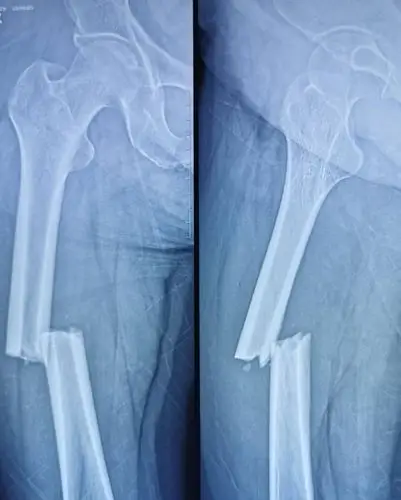

股骨干合并股骨颈骨折一例